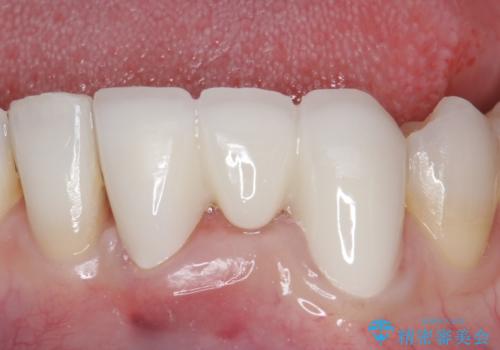

- 他院にて矯正治療を行ったが、左下の前歯の見た目が気になるのでセラミックで治したいといらっしゃった方の症例です。

左下123番のブリッジになるが、左下1番と3番の歯軸が合っておらず神経治療が必要になる可能性があるため部分矯正を提案したところ、希望されなかったため、そのままの歯軸でオールセラミッククラウンによる補綴を行いました。

今回用いたオールセラミッククラウンはジルコニアフレームという白い素材の上にセラミックを盛っているため、審美性が非常に高いのが特徴です。

また、ジルコニアは人工ダイヤモンドの材料にも使われているほど高い強度を持っており、そのためオールセラミッククラウンは審美性だけでなく、奥歯やブリッジの補綴も可能とするクラウンです。